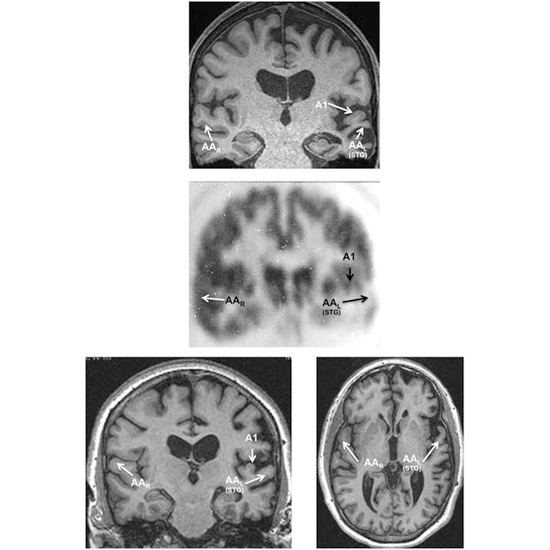

Під час проведення магнітно-резонансної томографії головного мозку пацієнтки виявлена значна асиметрична атрофія у лівій півкулі, що охоплювала нижню лобову звивину, нижню тім’яну ділянку, а також всі ділянки лівої скроневої частки, включаючи верхню скроневу звивину і передню скроневу частку. Звивина Гешля виявилася відносно збереженою, тоді як слухова асоціативна кора головного мозку — атрофованою.

55-річний чоловік зазначав, що протягом останніх трьох років мав труднощі із підбором слів. У його мовленні було багато пауз та «ухильного» стилю. Подібний «ухильний» стиль мовлення утруднював оцінку його граматичної структури. Моторні порушення мовлення були відсутні. Розуміння речень, заснованих на знайомих йому словах, зберігалося у слуховій та візуальній модальностях, за винятком тих, що були синтаксично складними. Клінічна картина відповідала логопенічній формі ППА. Результат тестування BNT становив 23% для усних відповідей та 43% — для письмових. Коли пацієнтові були представлені геометричні фігури, він не зміг в усній формі назвати куб, трикутник та прямокутник, а також не зміг правильно ідентифікувати ту чи іншу фігуру, почувши відповідне до неї слово, що свідчило про порушення слухового сприйняття іменників. Проте він міг правильно написати назви фігур, демонструючи, що наявність проблем із пошуком та сприйняттям слів були вибірковими саме для слухової модальності. Результати магнітно-резонансної томографії (МРТ) продемонстрували асиметричну атрофію лівої нижньої тім’яної частки. Позитронно-емісійна терапія продемонструвала відносно збережений метаболізм у звивині Гешля, але тяжкий гіпометаболізм у слуховій асоціативній корі. Сімейний анамнез свідчив, що у його матері була діагностована «деменція» у віці 50 років. Посмертна аутопсія довела наявність ППА із лобово-скроневою частковою дегенерацією типу А.

55-річна пацієнтка помітила розвиток прогресуючих труднощів із підбором слів для висловлювання їх як в усній, так і в письмовій формах. Повсякденне життя та інші поведінкові реакції були відносно збережені. Мовлення було значно порушене (9 слів/хв), утруднене, переривчасте та аграматичне. Повторювання фраз та речень було порушене. У неї не відзначався слуховий або візуальний дефіцит у розумінні слів. Пацієнтці встановлено діагноз аграматичної форми ППА. Результат тестування BNT становив лише 27%. МРТ продемонструвала асиметричну атрофію із відносно збереженою звивиною Гешля. Однак гени GRN, TDP-43 і C9orf72 не мали мутацій, які спричиняють захворювання.